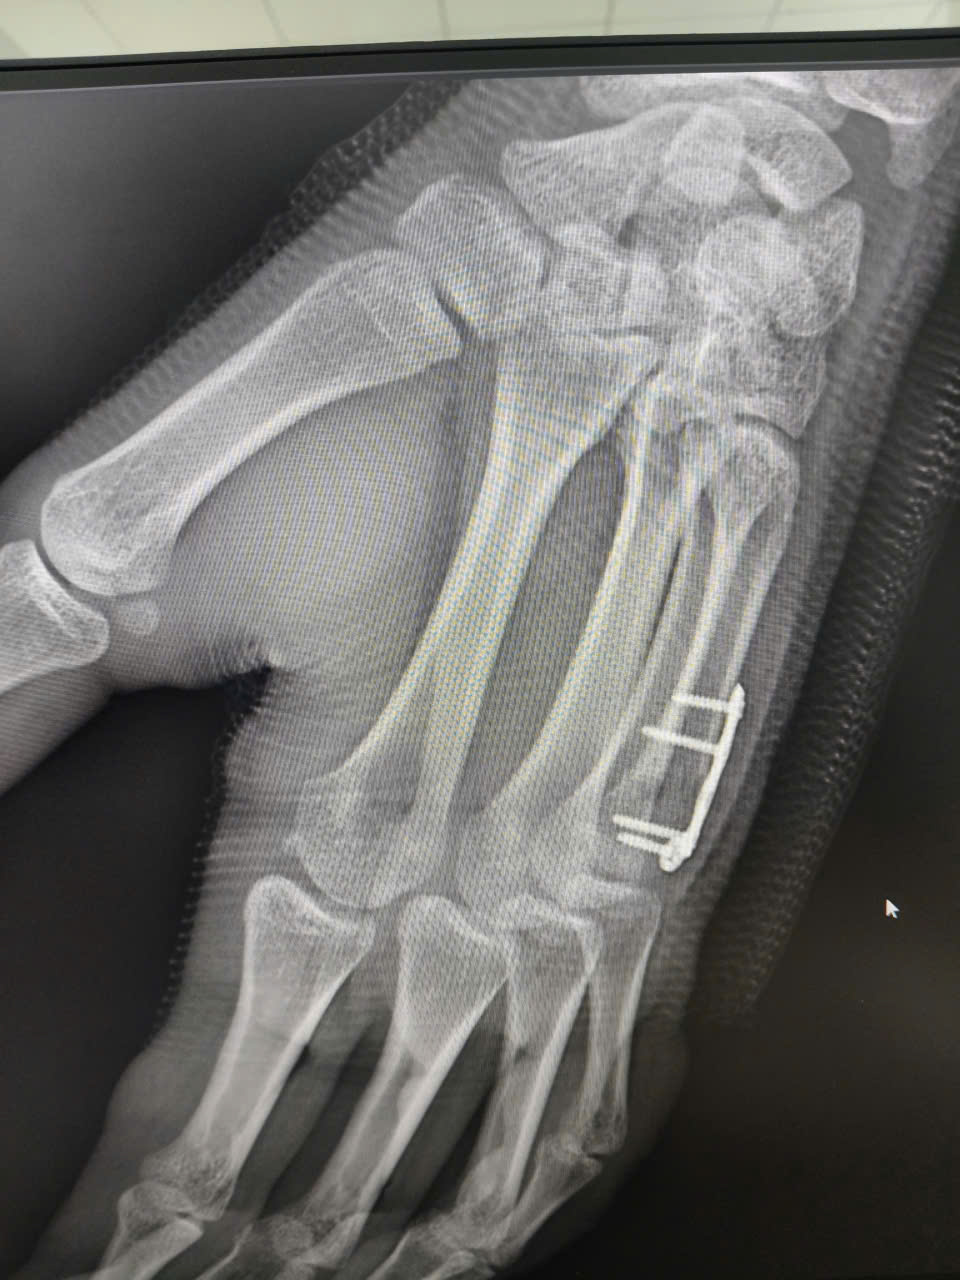

Ê-kíp phẫu thuật của Bệnh viện Đại học Y Dược, Đại học Quốc gia Hà Nội (cơ sở Linh Đàm) đã nhanh chóng thực hiện nắn chỉnh diện gãy và cố định xương bàn V bằng nẹp vít chuyên dụng cho bệnh nhân.

Ê-kíp phẫu thuật đã nhanh chóng thực hiện nắn chỉnh diện gãy và cố định xương bàn V bằng nẹp vít chuyên dụng. Một điểm sáng trong ca phẫu thuật này là nhánh cảm giác vùng mu tay của thần kinh trụ đã được bảo tồn nguyên vẹn, đảm bảo khả năng cảm giác cho bệnh nhân sau hồi phục.

Hình ảnh nẹp vít chuyên dụng ngón tay bị gãy của bệnh nhân.